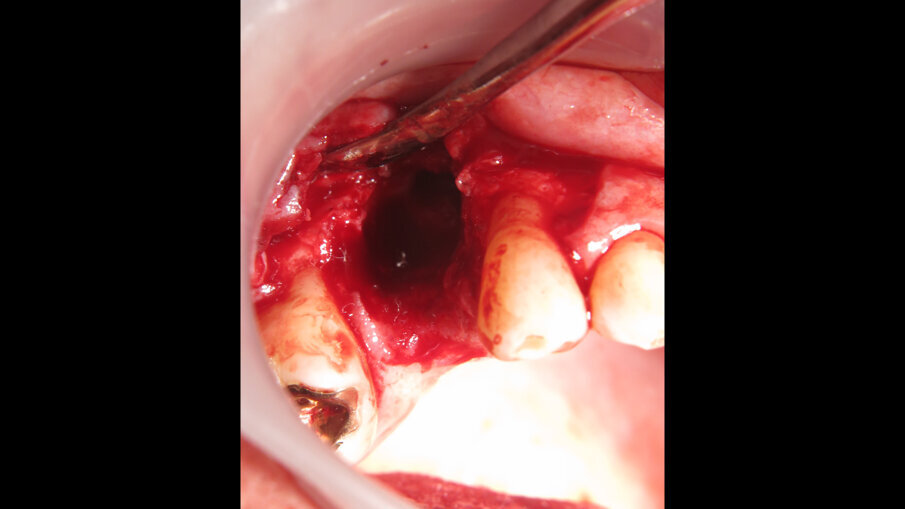

Implantáty byly zaváděny v lokální anestezii (40 mg Dexa­ratiopharm, intramuskulárně; ratiopharm) po premedikaci antibiotiky. Osteotomie byla postupně rozšiřována podle zamýšleného průměru implantátu. Po provedení incize byly odstraněny nekrotické nebo zánětlivé tkáně. Oblasti osteotomie byly preparovány postupnou sekvencí vrtáků podle doporučení výrobce. Implantáty byly zavedeny do oblastí preparované osteotomie za točivého momentu 45 Ncm.

Po chirurgickém zákroku byly pořízeny periapikální RTG snímky, na nichž byla zkontrolována přesnost zavedení implantátů. Pooperační medikace spočívala v předepsání antibiotik. Digitální RTG snímky byly pořízeny v době chirurgického zákroku, po 24 hodinách a jeden měsíc po zákroku, a to za účelem vyhodnocení úspěšnosti implantologického ošetření. Zánětlivé procesy byly zjištěny u 24,1 % pacientů. V případě potřeby byla provedena augmentace za použití materiálu NanoBone (Artoss), kostní náhražky Geistlich Bio­Oss a membrán Geistlich Bio-Gide (oba produkty Geistlich Biomaterials).